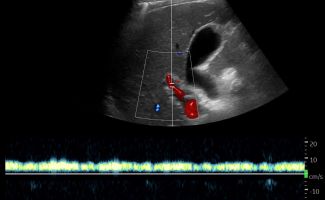

Με το Τriplex Σπληνοπυλαίου Άξονα αξιολογείται η πυλαία υπέρταση, συνήθως σε έδαφος χρόνιας ηπατοπάθειας και η βατότητα ή θρόμβωση της πυλαίας φλέβας και των ηπατικών φλεβών.